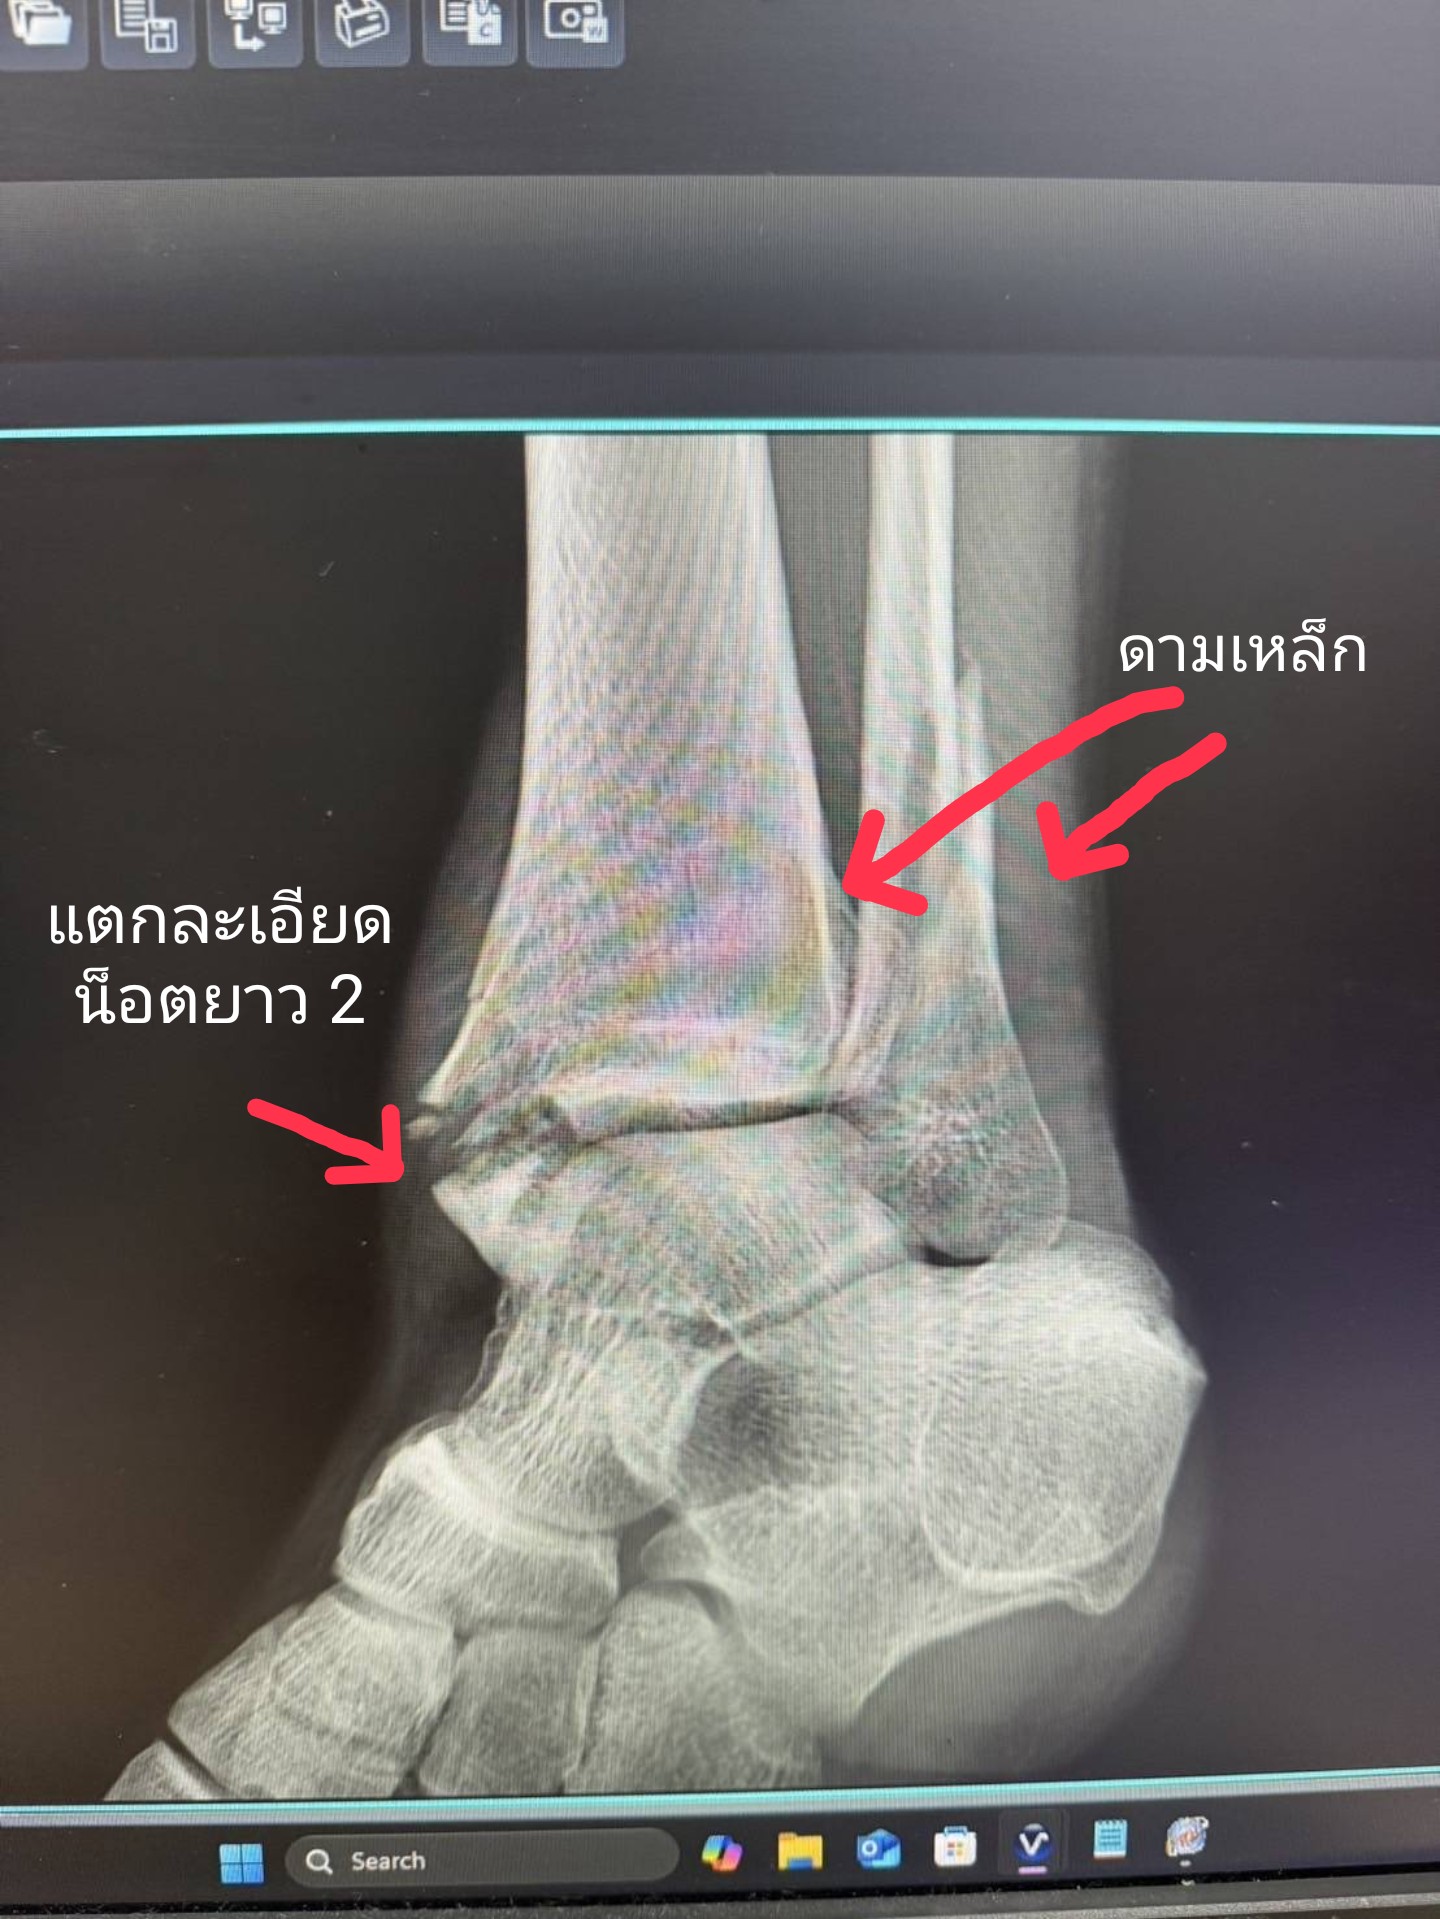

ข้อเท้าหัก

ผ่าตัด 2 ครั้ง ผ่าครั้งแรกใส่เหล็กพักได้ 1วัน หมอบอกดูฟิลม์เอกซเรย์น็อตยาวเข้าข้อผ่าแก้อีกรอบ ลล​แบบในภาพนานไหมครับกว่าจะเดินได้ ตอนนี้ผ่านมา 1 เดือนยังคงใส่เฝือกอ่อน และอยากทราบว่ากายภาพยังไงได้บ้างตอนนี้ ตอนไปพบแพทย์ครั้งแรกหลังจากออก รพ. หมอพูดด้วยแปบๆ และออกไป ยังไม่ทันได้ถามอะไรครับ